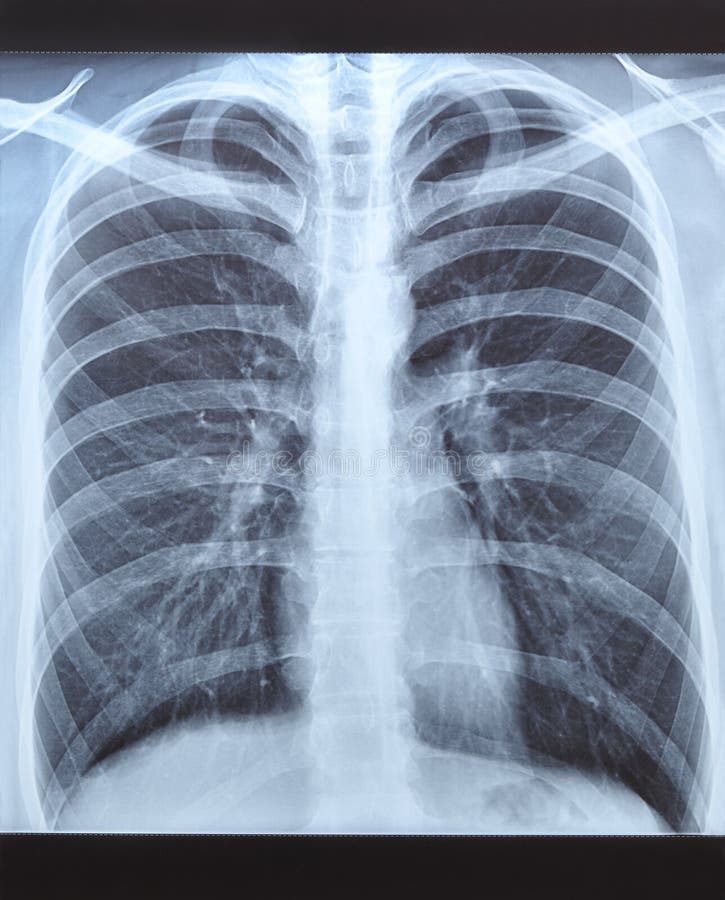

Рентген здоровых легких: примеры снимков и советы

Раздел: Сокровищница опыта